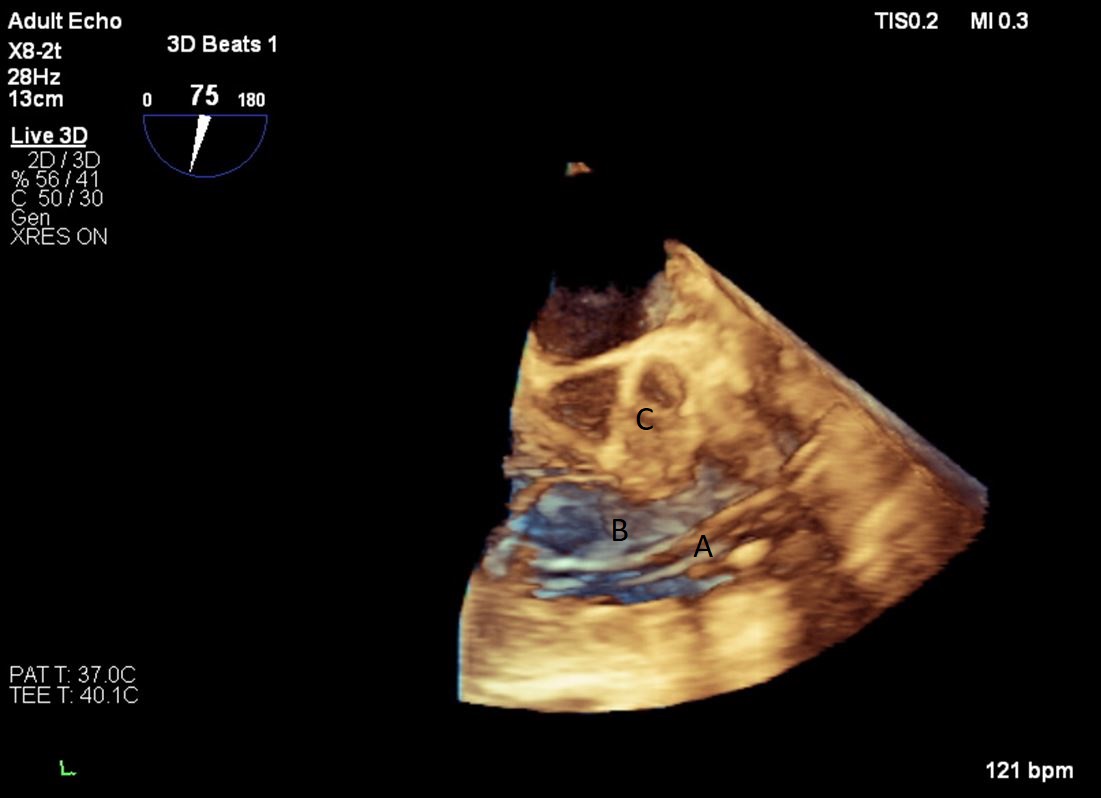

Fig. 24.Three-dimensional transesophageal echocardiographic image of the Medtronic-Hall valves in the mitral (A) and tricuspid valve (B) positions.

For patients who are not candidates for LVAD due to RV dysfunction, total artificial heart (TAH) is an alternative option for mechanical circulatory support. The SynCardia device has been FDA approved for advanced HF since 2004. It is a biventricular pneumatic pulsatile device comprising of two artificial ventricles. Each ventricles has an inflow (Figs. 23,24) and outflow valve (Medtronic-Hall, single tilting disc valve) [59].

Fig. 23.Mid-esophageal 4-chamber view with both Medtronic-Hall valves; Mitral (A) and Tricuspid (B) of the TAH visualized.